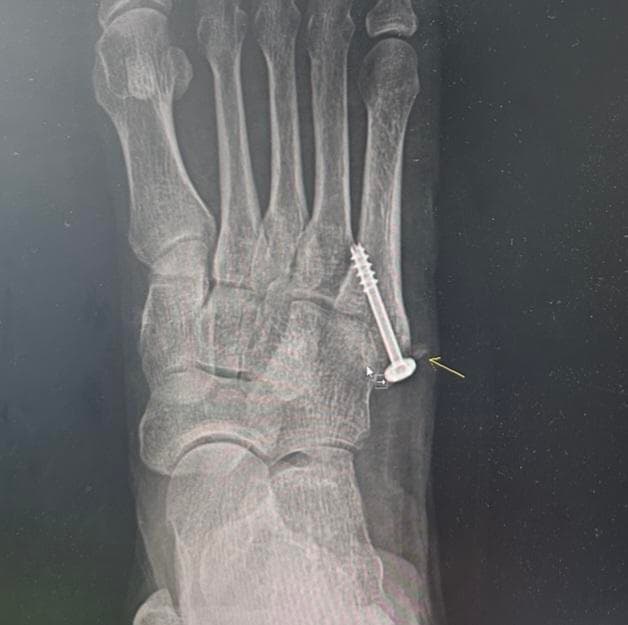

어머니께서 약 2주전 새끼발가락-발등 부근을 수술하셨습니다. 첨부한 x레이 사진처럼 수술하였는데 상처 염증등으로 실밥을 풀지 못해 퇴원이 미뤄지던 중 요근래 호전되어 내일모레쯤 실밥을 풀고 퇴원할 예정이었으나 갑자기 수술 엑스레이를 보여주며 사진의 화살표 표시한 부분처럼 뼛조각이 남아있는걸 이제 알았고, 약 1년 뒤 나사를 빼며 제거해주겠다고 합니다.

그 뼛조각이 아예 떨어져나가있는 것인지 발가락 뼈에 약간 붙어는 있는 것인지 병원측에서도 모르겠다고 하였는데 이를 1년간 그대로 둔다면 어떤 문제가 발생할 수 있는지 궁금합니다.

어머니께서 2주전에 새끼발가락 발등 부위에 수술을 받으셨고 엑스레이상 뼛 조각이 남아 있고 병원에서는 1년 뒤에 나사 제거할 때 함께 제거할거라고 했다면 그대로 뼛조각을 두었을 경우 잔여골편 같은 경우 정확히 어떤 문제를 일으킬 지는 알 수 없으며 관절 안에서 떠다니면서 마찰이나 염증 부종 관절의 움직임 제한이나 통증 저림 기능저하 및 연골의 손상이 발생할 수도 있고 혹은 뼈가 안정적으로 붙는다면 큰 문제가 발생하지 않을 수도 있습니다.

일단 퇴원전에 진료기록 사본 및 수술기록지 정밀한 영상자료등을 미리 준비 해놓고 수술 중에 발생한 것인지 수술 후에 떨어진 것인지 명확히 물어보고 기록해두시는게 좋을 것으로 생각됩니다.